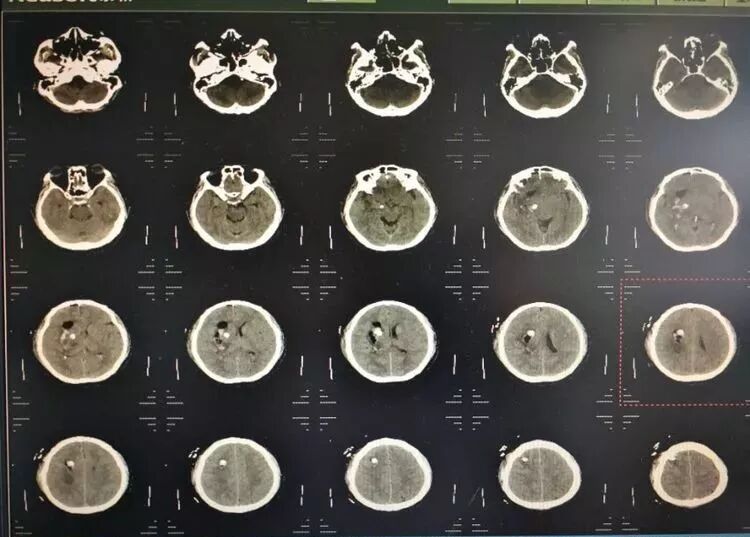

患者男性,53岁,以右侧基底节出血为诊断入院,量约50毫升。

术前片子

术后第一天复查,患者清醒,言语正常。